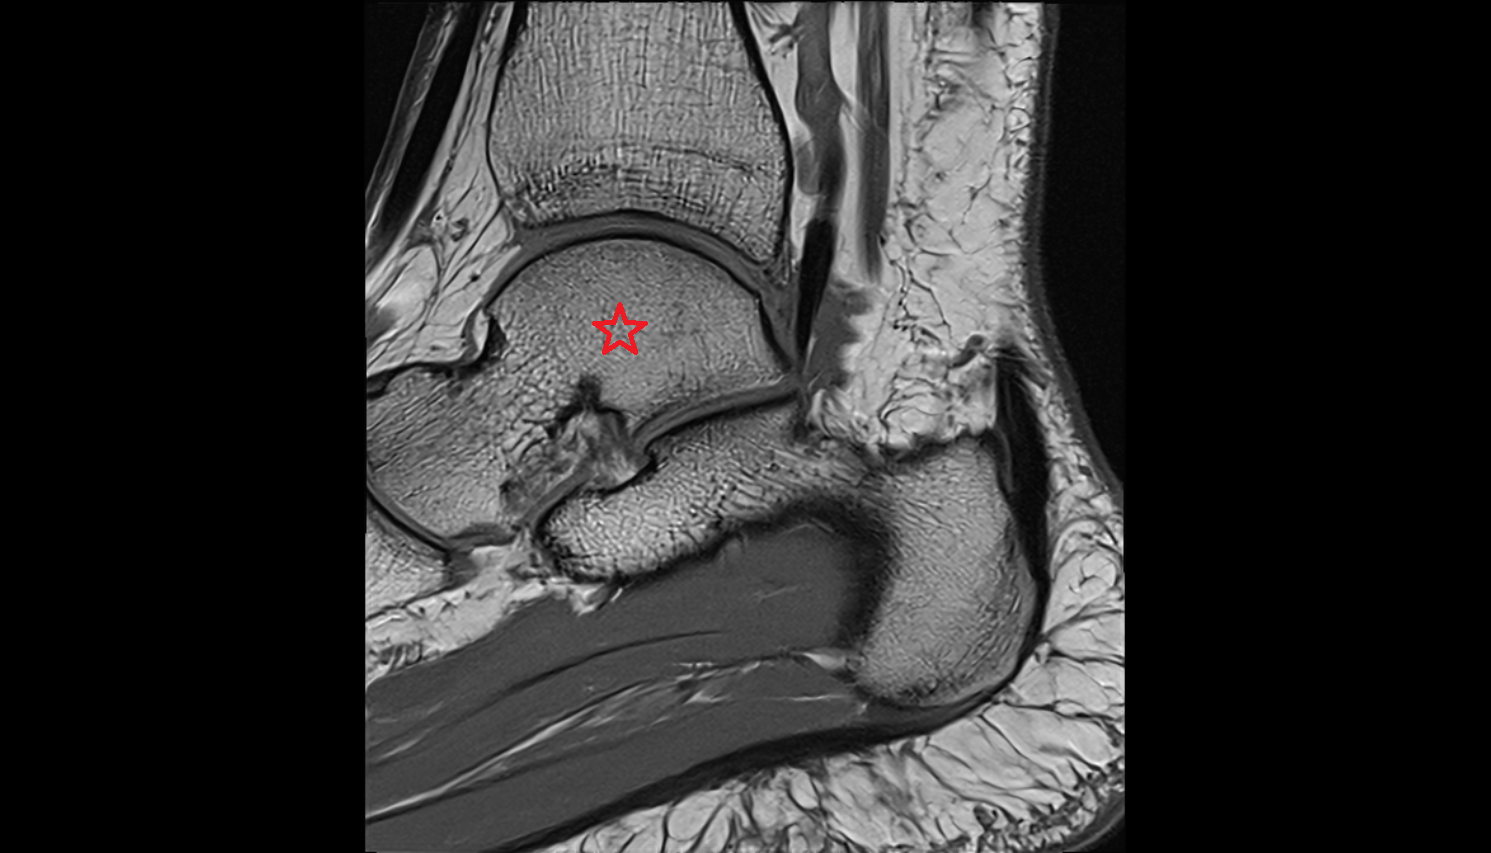

- Talus

- Head of talus

- Body of talus

- Neck of talus

- Calcaneus

- Sustentaculum tali

- Ankle joint

- Talocalcaneal joint

- Achilles tendon